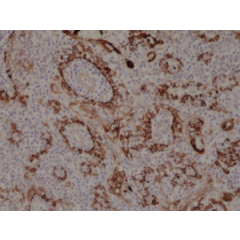

anti-Cytokeratin-18 (human), Rabbit Monoclonal (RM279)

anti-Cytokeratin-18 (human), Rabbit Monoclonal (RM279)

REV-31-1162-00 REV-31-1162-00-R100 100 µl CHF 468.00